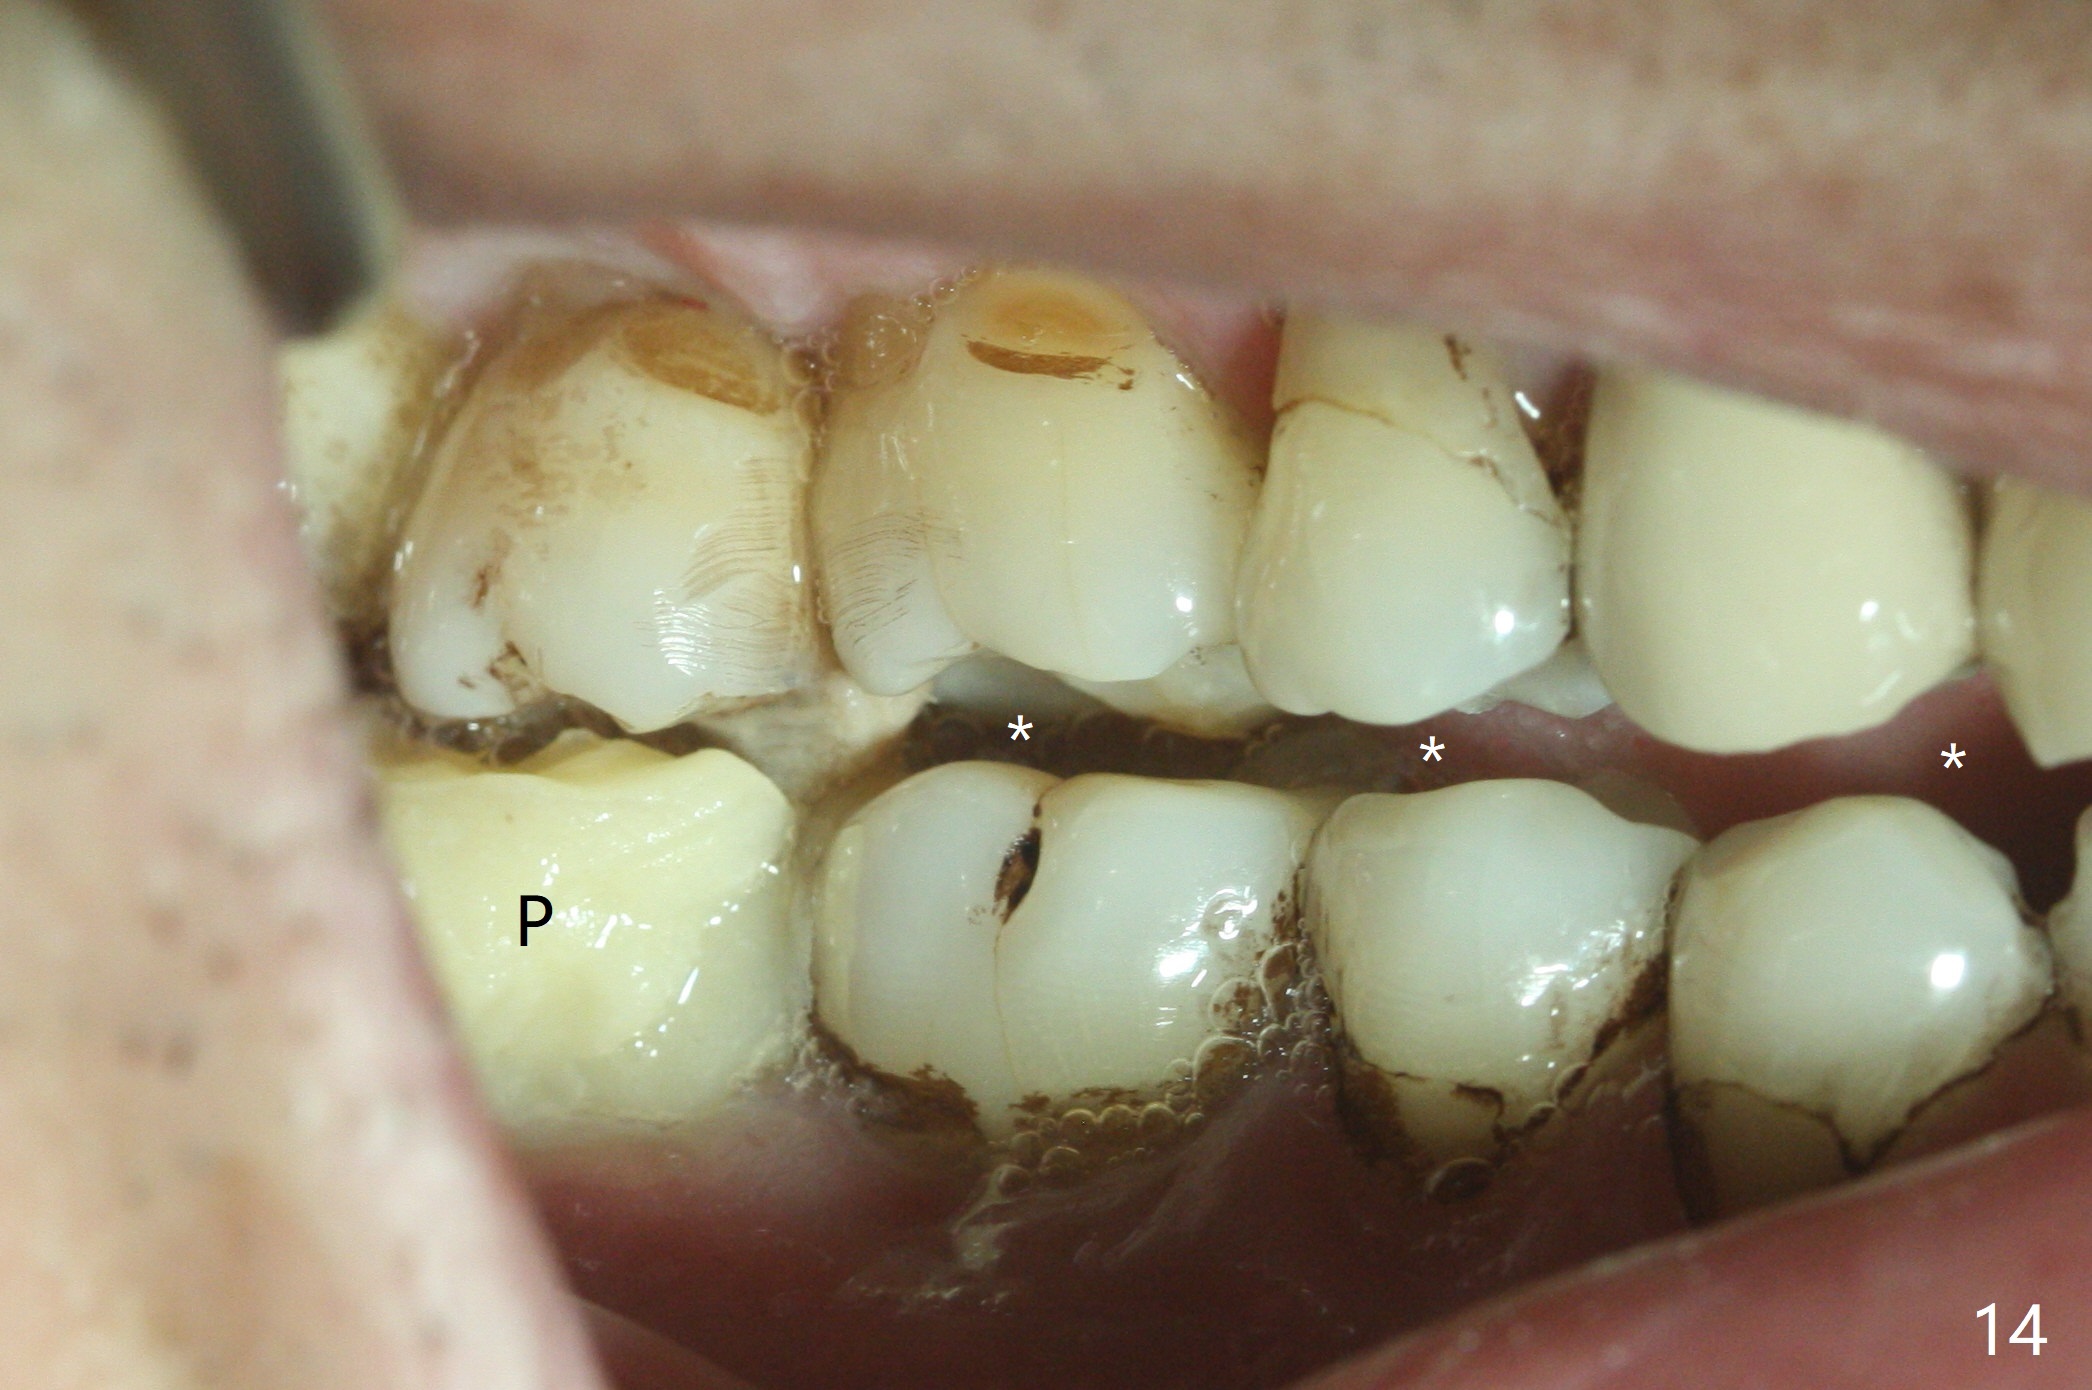

The buccal implant becomes loose in 2-3 months. When the wound heals (Fig.9 <), a 1.6x`10 mm implant is placed with the help of PAs for trajectory (Fig.10,11) and in the nonkeratinized gingiva (higher, the crestal bone may have been traumatized by previous implant placement, Fig.12). Two months later, the tooth #2 is partially intruded (Fig.13). A provisional (Fig.14 P) is fabricated in the osteointegrated implant at #31 with supraocclusion so that the remaining dentition has no occlusal contact (*). The periodontally compromised tooth #2 becomes in buccoversion in 2 months. The provisional is removed, while a lingual button is placed in the buccal surface of the tooth #2 (Fig.15). With power chain attached to the lingual mini-implant, the tooth #2 is lingualized in 2 months. The provisional and the implants are reused for final intrusion (Fig.16). The treatment is nearly 11 months. The buccal implant, although placed in the movable mucosa, remains stable and healthy (Fig.17). The tooth #1, as a guiding plane (to prevent #2 from distalization during intrusion), is not extracted after intrusion is completed.